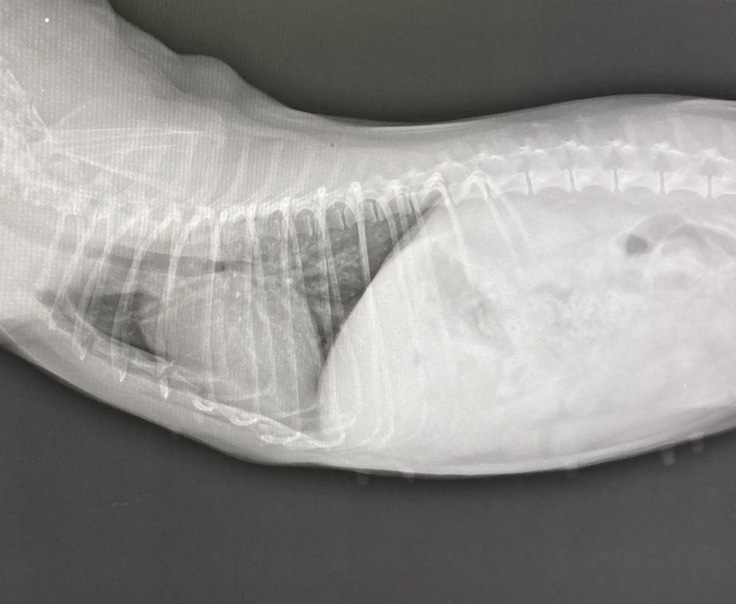

検査内容はレントゲンと血液検査です。

心配していた肝臓の数値は正常値に戻り、レントゲンでも肝臓は元の位置にとどまっており術後問題無いとの事でしたので、ひとまず安心しました😭💦

☆7月28日レントゲン写真